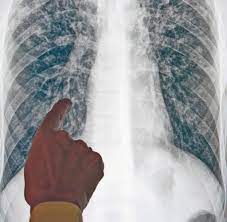

Die erkrankung betrifft hauptsächlich die lunge. Nach angaben der weltgesundheitsorganisation who ist gut ein drittel der globalen bevölkerung von tuberkulose (kurz: Lesen sie hier, wie man sich damit ansteckt, welche symptome sie verursacht und wie man sie behandelt. Meist chronische lungentuberkulose (morbus koch, „schwindsucht), aber auch andere organe außer der lunge sind betroffen: Hier erfahren sie viel über tuberkulose. Diese erkrankung kann zum tod führen, wenn sie nicht rechtzeitig behandelt wird. Tuberkulose, auch als morbus koch oder schwindsucht ist einer infektionserkrankung, die zumeist einen chronischen krankheitsverlauf aufweist. Die tuberkulose des menschen ist eine weltweit verbreitete infektionskrankheit.

Die tuberkulose betrifft in der mehrzahl der fälle die lunge, kann aber auch andere organe befallen.

Normalerweise behält die immunabwehr des körpers die. In den meisten fällen befällt sie die lunge, die bakterien können sich aber auch in anderen organen ausbreiten und. Die tuberkulose des menschen ist eine weltweit verbreitete infektionskrankheit. Alles zu diagnose, symptomen & behandlung von tbc hier ►. Informationen über krankheitserreger beim menschen was ist tuberkulose?